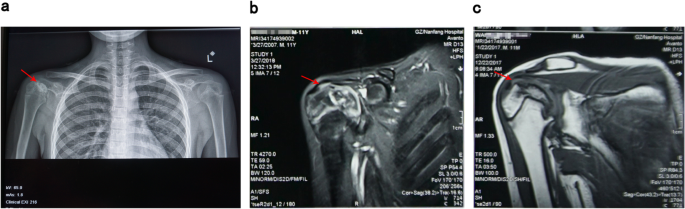

Wang, a 6-year-old boy, was hospitalized with “a week of limb aches after activities” in 2013, and was comprehensively diagnosed with “aplastic anemia” and then treated with cyclosporine (50 mg, bid). After genetic compatibility test, he was found to match his sister’s human leukocyte antigen (HLA) 10/10, so the allogeneic hematopoietic stem cell transplantation was successfully performed on June 2nd, 2016 (9 years old). The implantation rate was examined to be 85 % using fluorescence in situ hybridization (FISH) at 3 months after transplantation. He began to take methylprednisolone tablets (12 mg, bid), cyclosporin tablets (75 mg, bid) and mycophenolate mofetil tablets (250 mg, bid) after transplantation. Methylprednisolone tablets started to decrease after maintaining the dose for about half a year. In January 2017, the dosage of methylprednisolone tablets was reduced to 8 mg, bid, and then 4 mg, bid in February, and stopped in March. He persistently took cyclosporine (75 mg, bid) and mycophenolate mofetil tablets (250 mg, qd) since the transplantation. He didn’t take tacrolimus capsules (2.5 mg, tid), sirolimus tablets (1 mg, qd) and calcium carbonate D3 (1 tablet, qd) until rejection occurred in November 2017. In January 2018, he was diagnosed with “keratitis” due to photophobia and hyperemia in his left eye without obvious cause. Cytomegalovirus viral load DNA copy number was tested and in normal range (< 500 IU/ml). He received the therapy of ganciclovir (150 mg, bid), methylprednisolone (2 mg, bid) and cyclosporine (25 mg, qd) for the consideration of viral infection and chronic graft versus host disease (GVHD) after transplantation. Three months later, due to the pain and discomfort of both hips, he underwent bilateral hip X-ray and magnetic resonance examinations at the local hospital, which showed bilateral necrosis of the femoral osteoepiphysis (Fig. 1).

Subsequently, he was hospitalized again with “keratitis”, “aplastic anemia after hematopoietic stem cell transplantation”, and “bilateral necrosis of the femoral osteoepiphysis”. During his stay in the hospital, the drug concentrations of cyclosporine were monitored as CsA 175.00ng/ml and CsA 102.10ng/ml respectively on April 3rd and 9th, 2018, which normal level ranges from 100 to 200ng/ml. After admission to the hospital, ganciclovir (150 mg, bid), methylprednisolone (2 mg, bid) and cyclosporine (75 mg, bid) were given to alleviate graft-versus-host reaction, and then his visual acuity gradually improved. Methylprednisolone was discontinued after one month, and he was discharged on April 29th after his condition improved. After discharge, he continued taking the post-transplant medication. On May 22nd, he was hospitalized again with “two days of sore throat” with a large area of ulcer in his oral cavity. After treated with rituximab (5 mg, qw, 4 times in total), he continued to receive ganciclovir (150 mg, bid) antiviral treatment, and then his oral ulcers gradually improved. On May 26th, He developed the symptom of macroscopic hematuria, and urine routine examination showed positive urinary protein (1+) and positive urine occult blood (3+), while other indexes were normal. Blood analysis was reviewed on May 28th, and tacrolimus drug concentration was monitored as FK 506 11.60ng/ml (normal range: 5-10ng/ml), and sirolimus dose was adjusted at the same time of excluding infection. Blood routine test was reviewed on June 3rd, and he was treated with rituximab again. The treatment went on smoothly and the symptom of macroscopic hematuria was better than before. He was discharged on June 4th and continued to take the post-transplant medication. After discharge, he still felt painful in joints and could not walk easily. Worried about the deterioration of his condition, he was hospitalized in the First Affiliated Hospital of Guangzhou University of Chinese Medicine on June 19th. He complained of pain in movements of the hips, knees and ankles at admission, which was relieved after rest. After physical examination, he was found to have the following signs: multiple pigmentation spots throughout the body, keratitis, declining vision, softening of nails and toenails, limited rotation of both hips, double knee joint internal and external roll test (+), limited dorsal extension of ankle joints (Fig. 2). X-ray examinations of the shoulders, hips, knees and ankles and magnetic resonance examinations of the shoulders, knees and ankles were performed subsequently (Figs. 3 and 4), indicating epiphyseal necrosis of bilateral humeral heads and femoral heads, talus osteonecrosis, and femoral condyle bone infarction. Suffering from the disease at the age of 9, the 11-year-old child’s weight is stable at about 30 kg now, which is in line with the normal weight, indicating that there is no overweight and malnutrition for him. Since his transplantation in 2016, he began to take a large amount of glucocorticoids and anti-rejection drugs for a long period of time. During the past two years, every time the child took glucocorticoids, he was accompanied by pain in the hips, knees and ankles, which was relieved after the drug withdrawal. According to the analysis of his concrete condition, it is suspected that there could be a certain timeliness between necrosis of the femoral head and taking large doses of glucocorticoids (see Table 1).

Although increasing studies on the etiology or pathogenesis of Perthes disease have been performed for the past several decades, the causes of Perthes disease still remain unclear. In this case, with MRI examination finding the epiphyseal necrosis of right humeral head, femur and tibia, and X-ray examination finding bilateral femoral head necrosis, the child was diagnosed as Perthes disease based on his clinical and imaging data. And we suppose that long-term and high-dose glucocorticoids may be one of the causes of Perthes disease. It is generally recognized that excessive glucocorticoids can cause femoral head necrosis in adults, but regarding the use of glucocorticoids causing Perthes Disease, this case report may be the first to put forward this view. The child in this case can be diagnosed as Perthes Disease, but further discussion is needed about/on whether it is caused by drugs, especially glucocorticoids. Through the analysis of the following aspects, it could be concluded that the main cause of Perthes disease for the child in this case is the long-term and high-dose use of glucocorticoids.